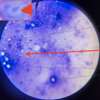

Trypanosoma sp.: Trypomastigote

Fish blood